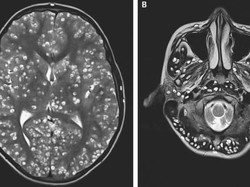

Bayi 8 Bulan Didiagnosis Penyakit Super Langka dan Belum Ada Obatnya

Bayi ini terdiagnosis penyakit yang sangat langka dan hingga kini belum diketahui apa obat dan penanganannya. Simak kisahnya dalam artikel berikut ini.